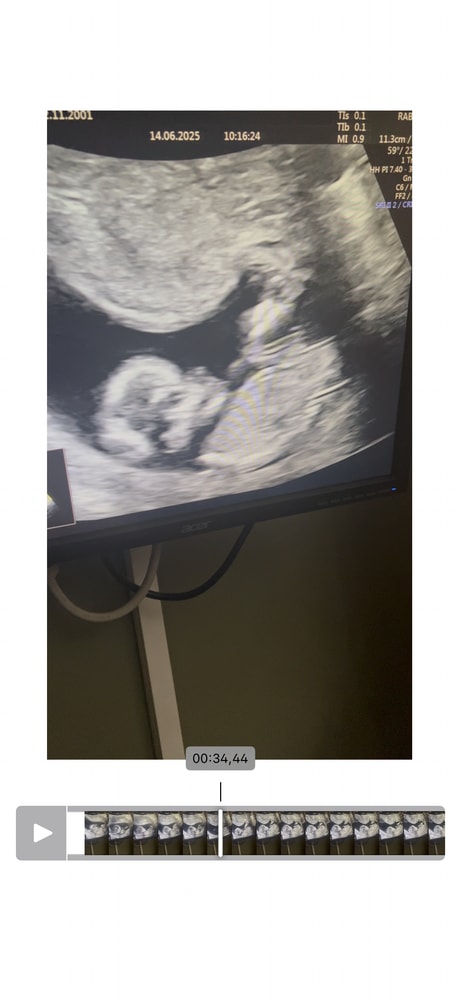

Гадание на пол ребёнка

1-ый триместр беременностиКак думаете? Давайте погадаем) просто ради интереса

Как по мне, вообще ничего не видно 🙈

Но пусть будет девочка, - моя тоже бугорок прикрывала ножкой))

Влада, да тут видно кофейное зернышко на всех фото 😄 ну и половой бугорок параллелен позвоночнику